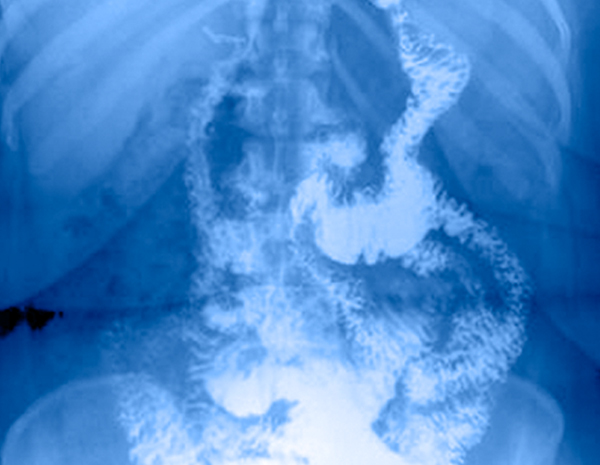

Este procedimiento bariátrico consiste en realizar una modificación anatómica del sistema digestivo. Más de 34 años de experiencia en este tratamiento hacen a esta técnica quirúrgica una de las más populares y exitosas en la historia de la bariatria. Consiste en reducir el estómago a una capacidad de 15 a 30 ml para después conectarlo al intestino delgado.

Ya que la comida salta un gran segmento del intestino delgado, se disminuye la absorción calórica y de nutrimentos del organismo. Además, debido al tamaño del estómago que se deja, se reduce la cantidad de comida que el paciente puede ingerir diariamente. Su estómago es mas pequeño y hace que sienta saciedad más rápidamente lo que hace que su apetito se reduzca para así comenzar a bajar de peso.